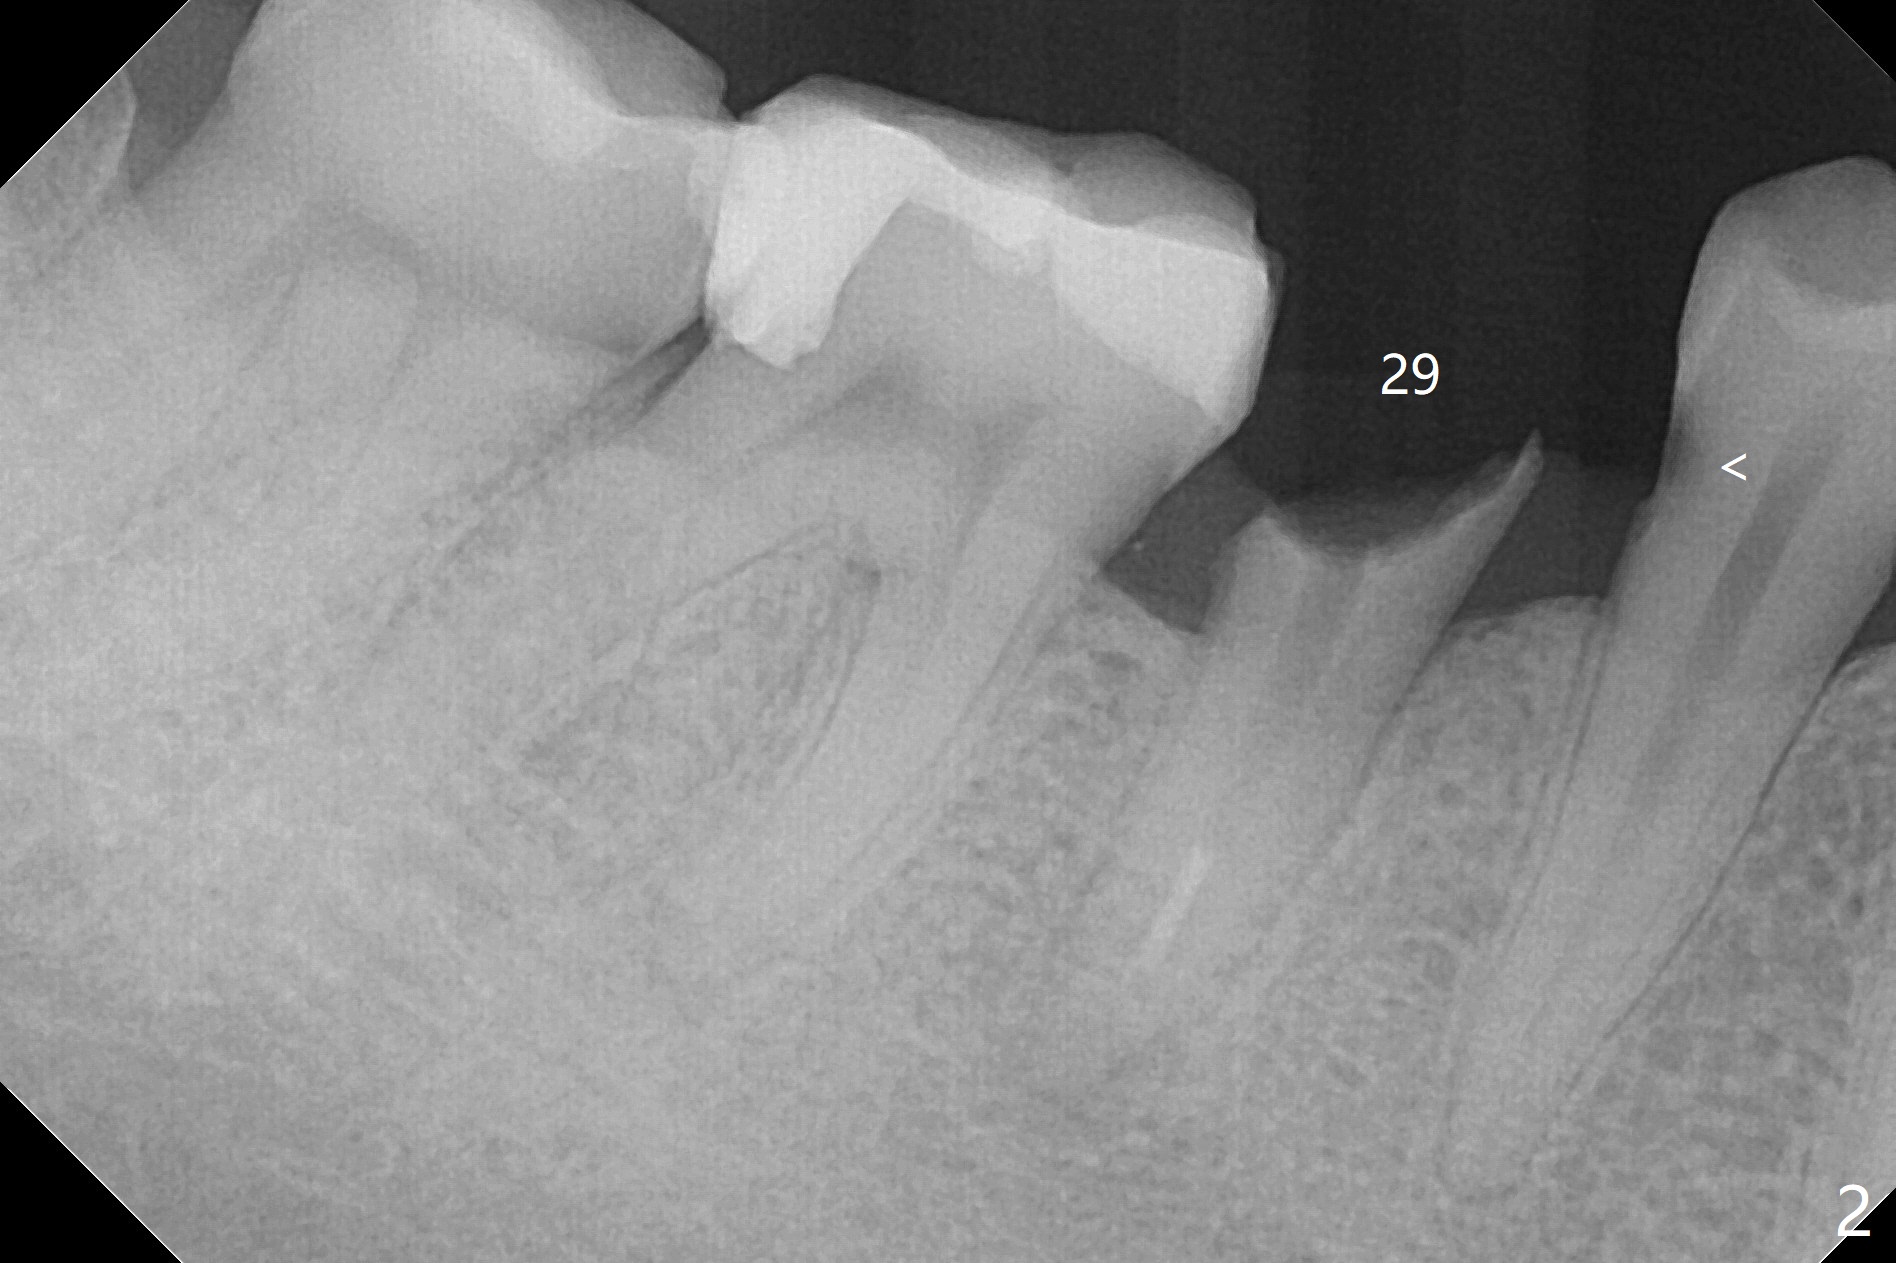

Equigingival Fracture M

A 38-year-old woman dislodged the crown and post of #29 with equigingival root (Fig.1) and incomplete RCT probably related to the curved and obliterated root tip (Fig.2). For restoration, it is the best to initiate osteotomy in the lingual slope of the socket (Fig.3). A 4 mm implant may be more appropriate than 3.5 mm one. Are we ready for free hand placement? Prepare gingival retraction cord for #28 distal cervical caries before surgery (Fig.2 <).